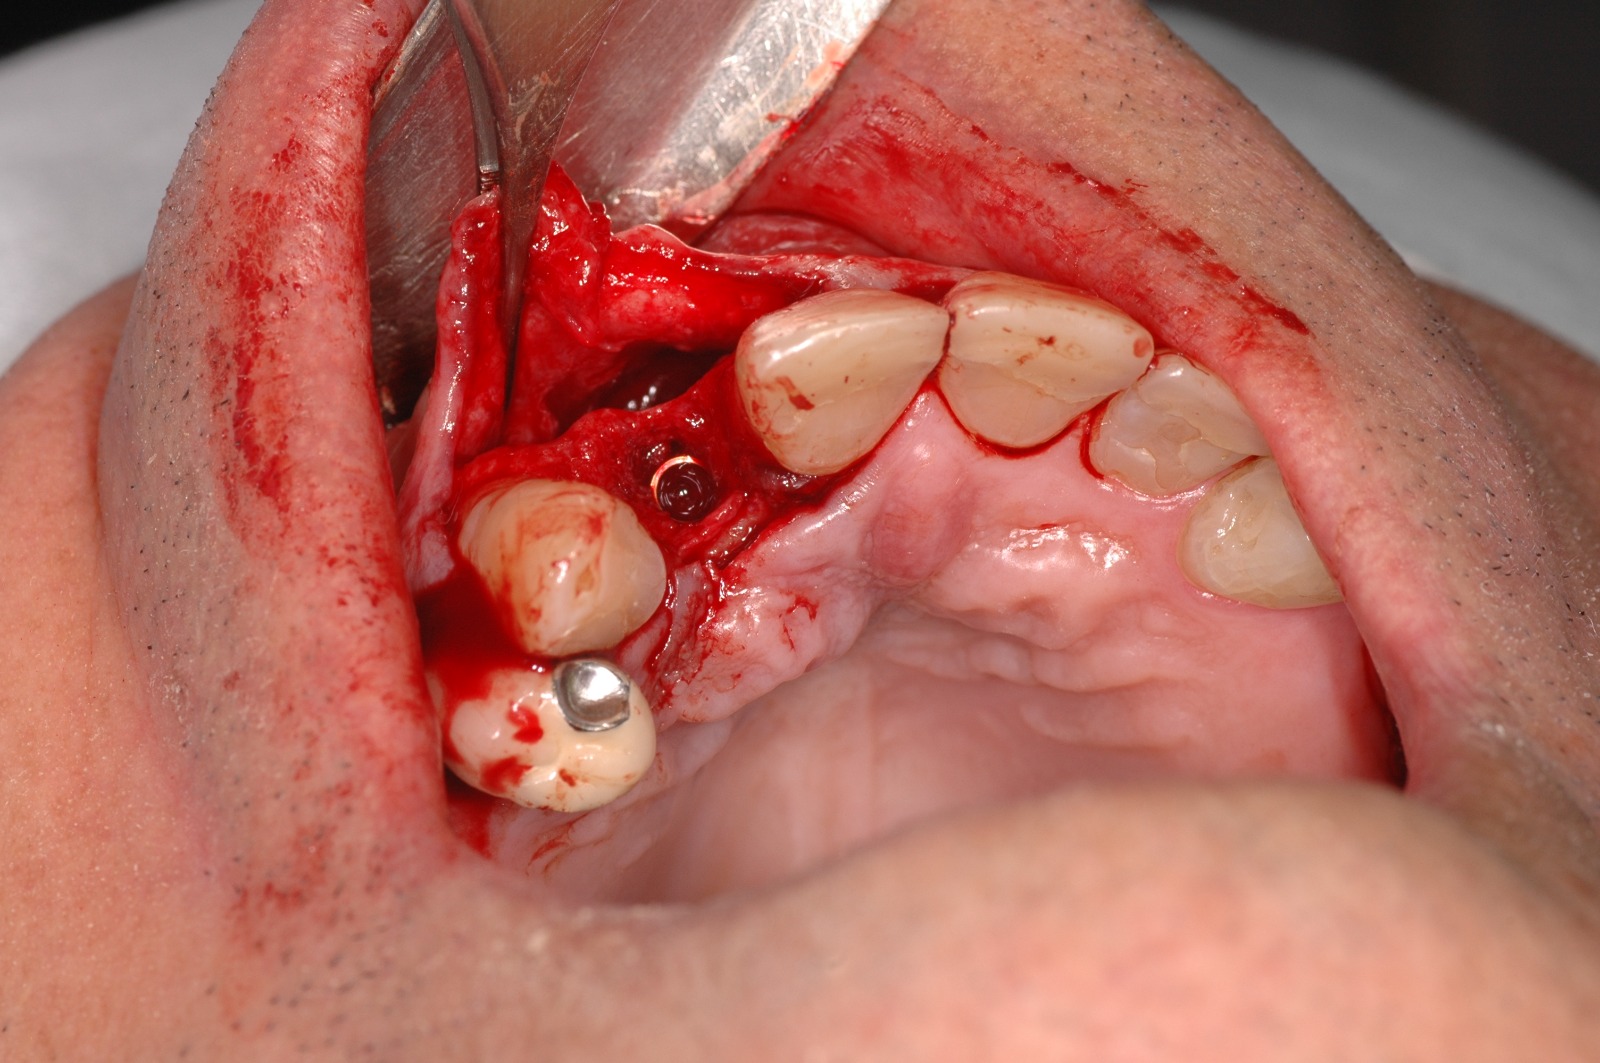

Regeneración ósea guiada

En algunos casos, puede ser necesario realizar un injerto óseo antes o durante la colocación de los implantes dentales. Esto se debe a que la cantidad o calidad del hueso puede no ser suficiente para soportar el implante de manera adecuada.

Casos Clínicos

Observa cómo la ciencia y la tecnología se unen para reconstruir el hueso perdido y devolver la confianza a quien la había perdido